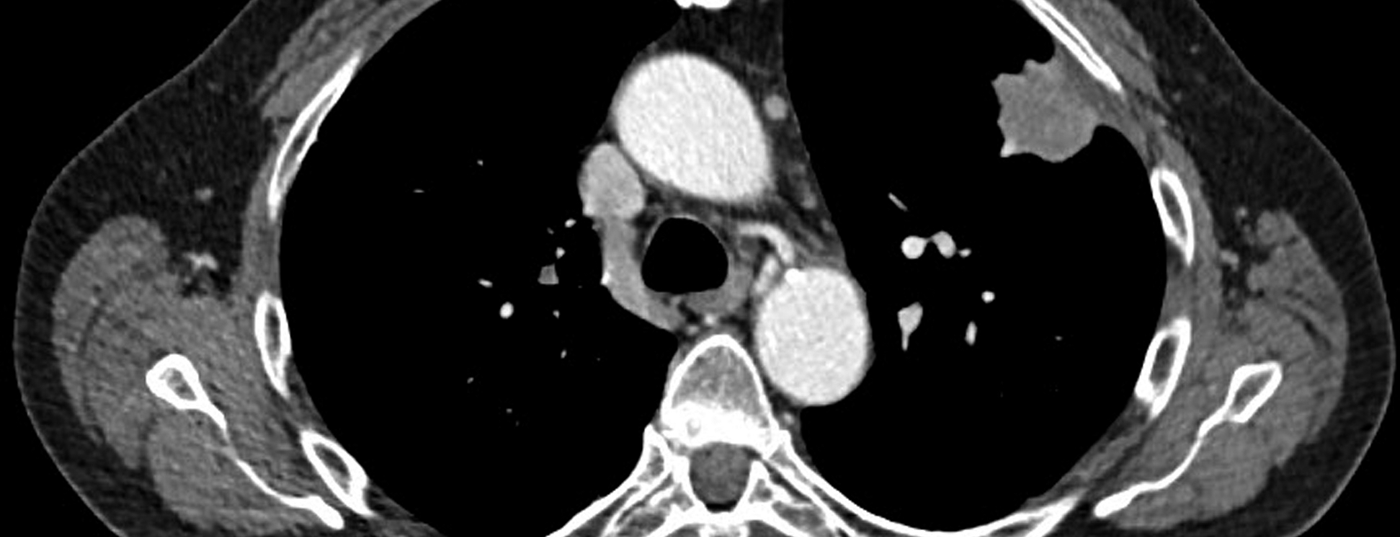

• Radiologische Abklärung bei Lungenkarzinom

Wann werden welche Instrumente eingesetzt?

Nach wie vor werden viele Lungenkarzinome erst in einem späten oder fortgeschrittenen und somit ­symptomatischen Stadium ­diagnostiziert. Aufgrund neuester Studiendaten ­haben diverse Fachgesellschaften positive Empfehlungen für ein Lungenscreening abgegeben, für dessen Durch­führung aber noch ­einige Fragen ungeklärt sind. Bei einem neu diagnostizierten Lungen­karzinom sollte zur korrekten TNM-Klassifizierung ­umgehend ein genaues, nicht-­invasives, präoperati­ves Staging durch­­­­geführt werden, zumal dieses den Rahmen für eine ­geeignete Therapie­findung resp. das weitere Patienten­management darstellt. Die Kenntnis der Vor- und Nachteile sowie der ­Limitationen der verschiedenen, nicht-invasiven ­bild­­gebenden Modalitäten spielt hierbei eine bedeutende Rolle.